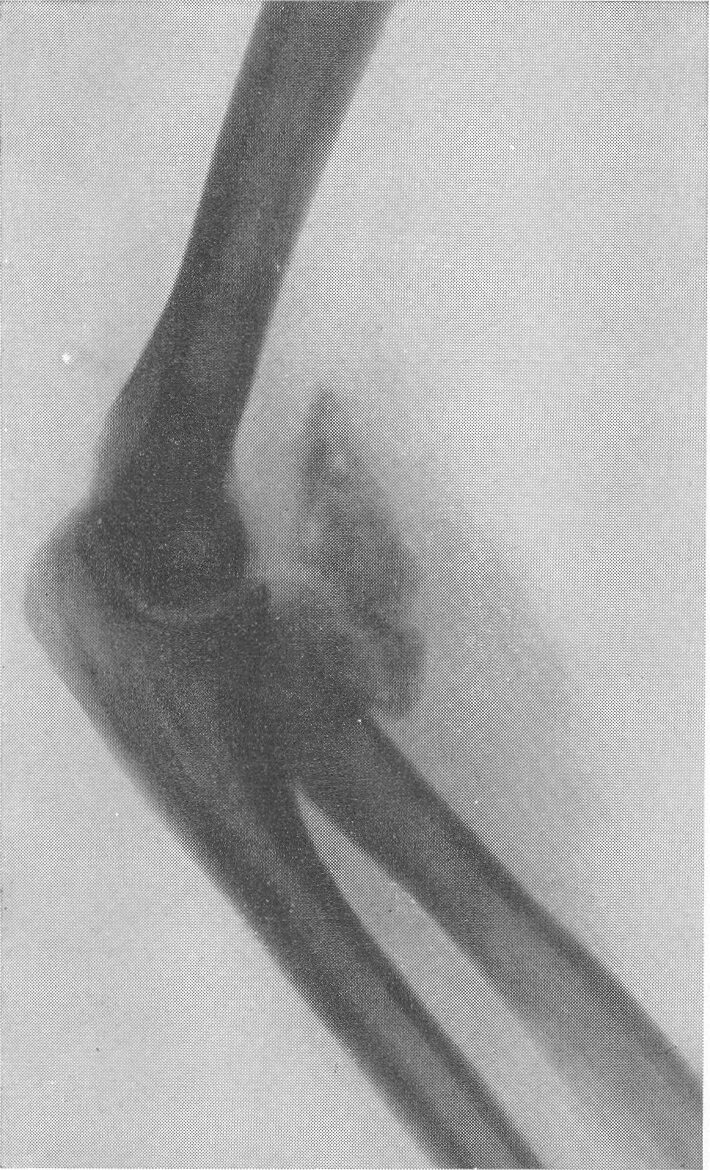

Оссифицированный миозит